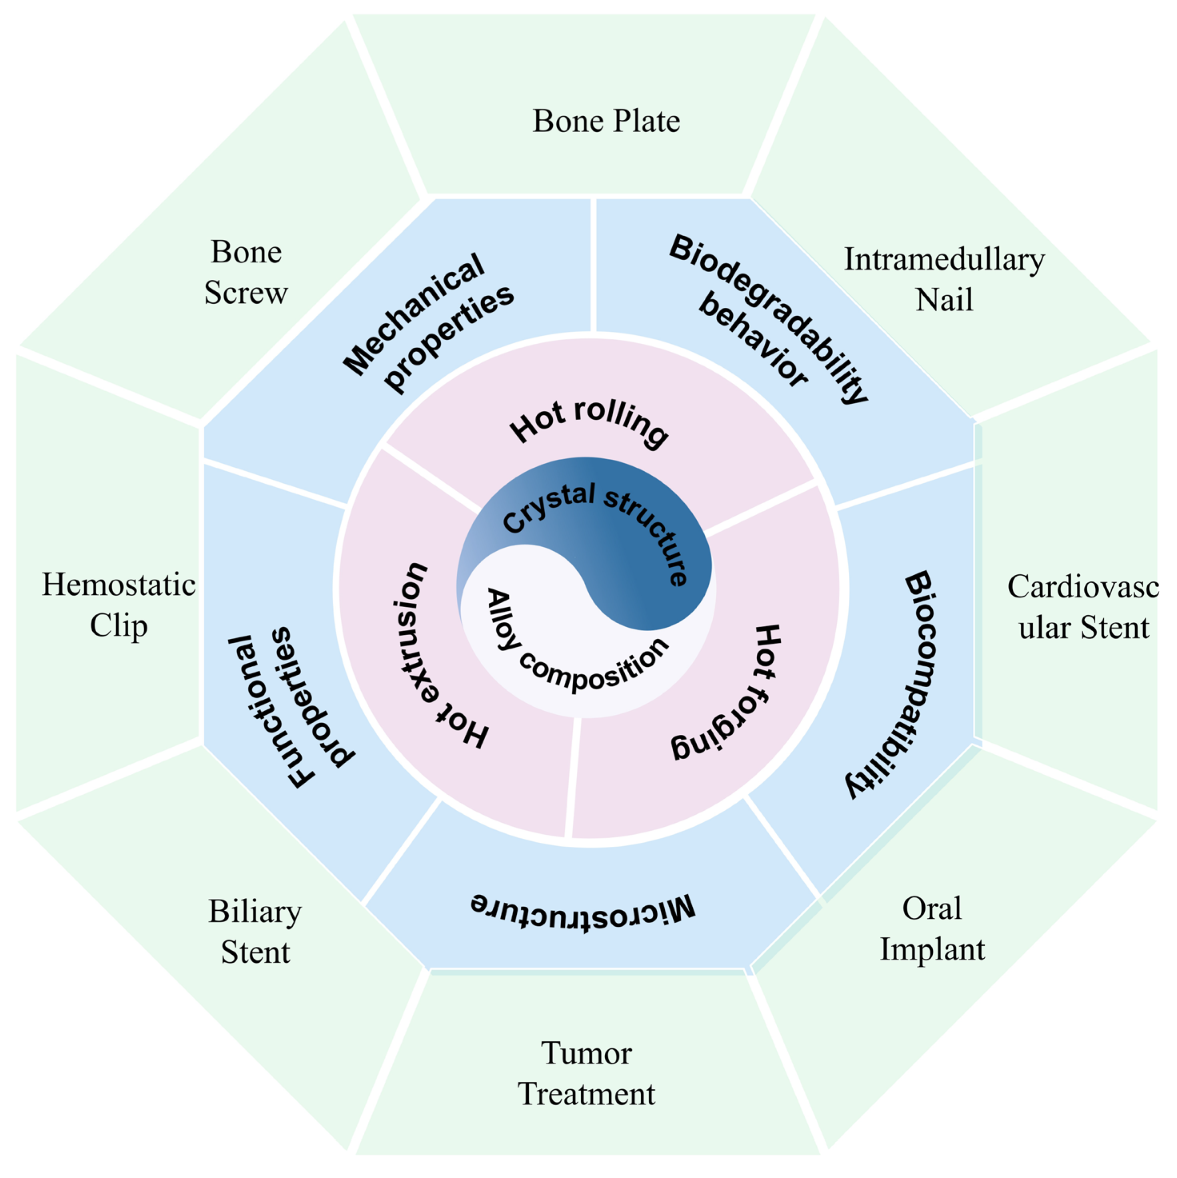

The Recent Developments of Thermomechanical Processing for Biomedical Mg Alloys and Their Clinical Applications

3. Applications of Biomedical Mg Alloy

3.1. Hemostatic Clip

3.2. Bone Screw

3.3. Bone Plate

3.4. Intramedullary Nail

3.5. Cardiovascular Stent

3.6. Oral Implant

3.7. Tumor Treatment

3.8. Biliary Stent

4. Conclusions